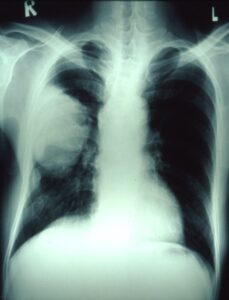

胸部X線で右肺の真ん中に大きな白い塊あり

肺がんと診断され、外科的切除が行われました